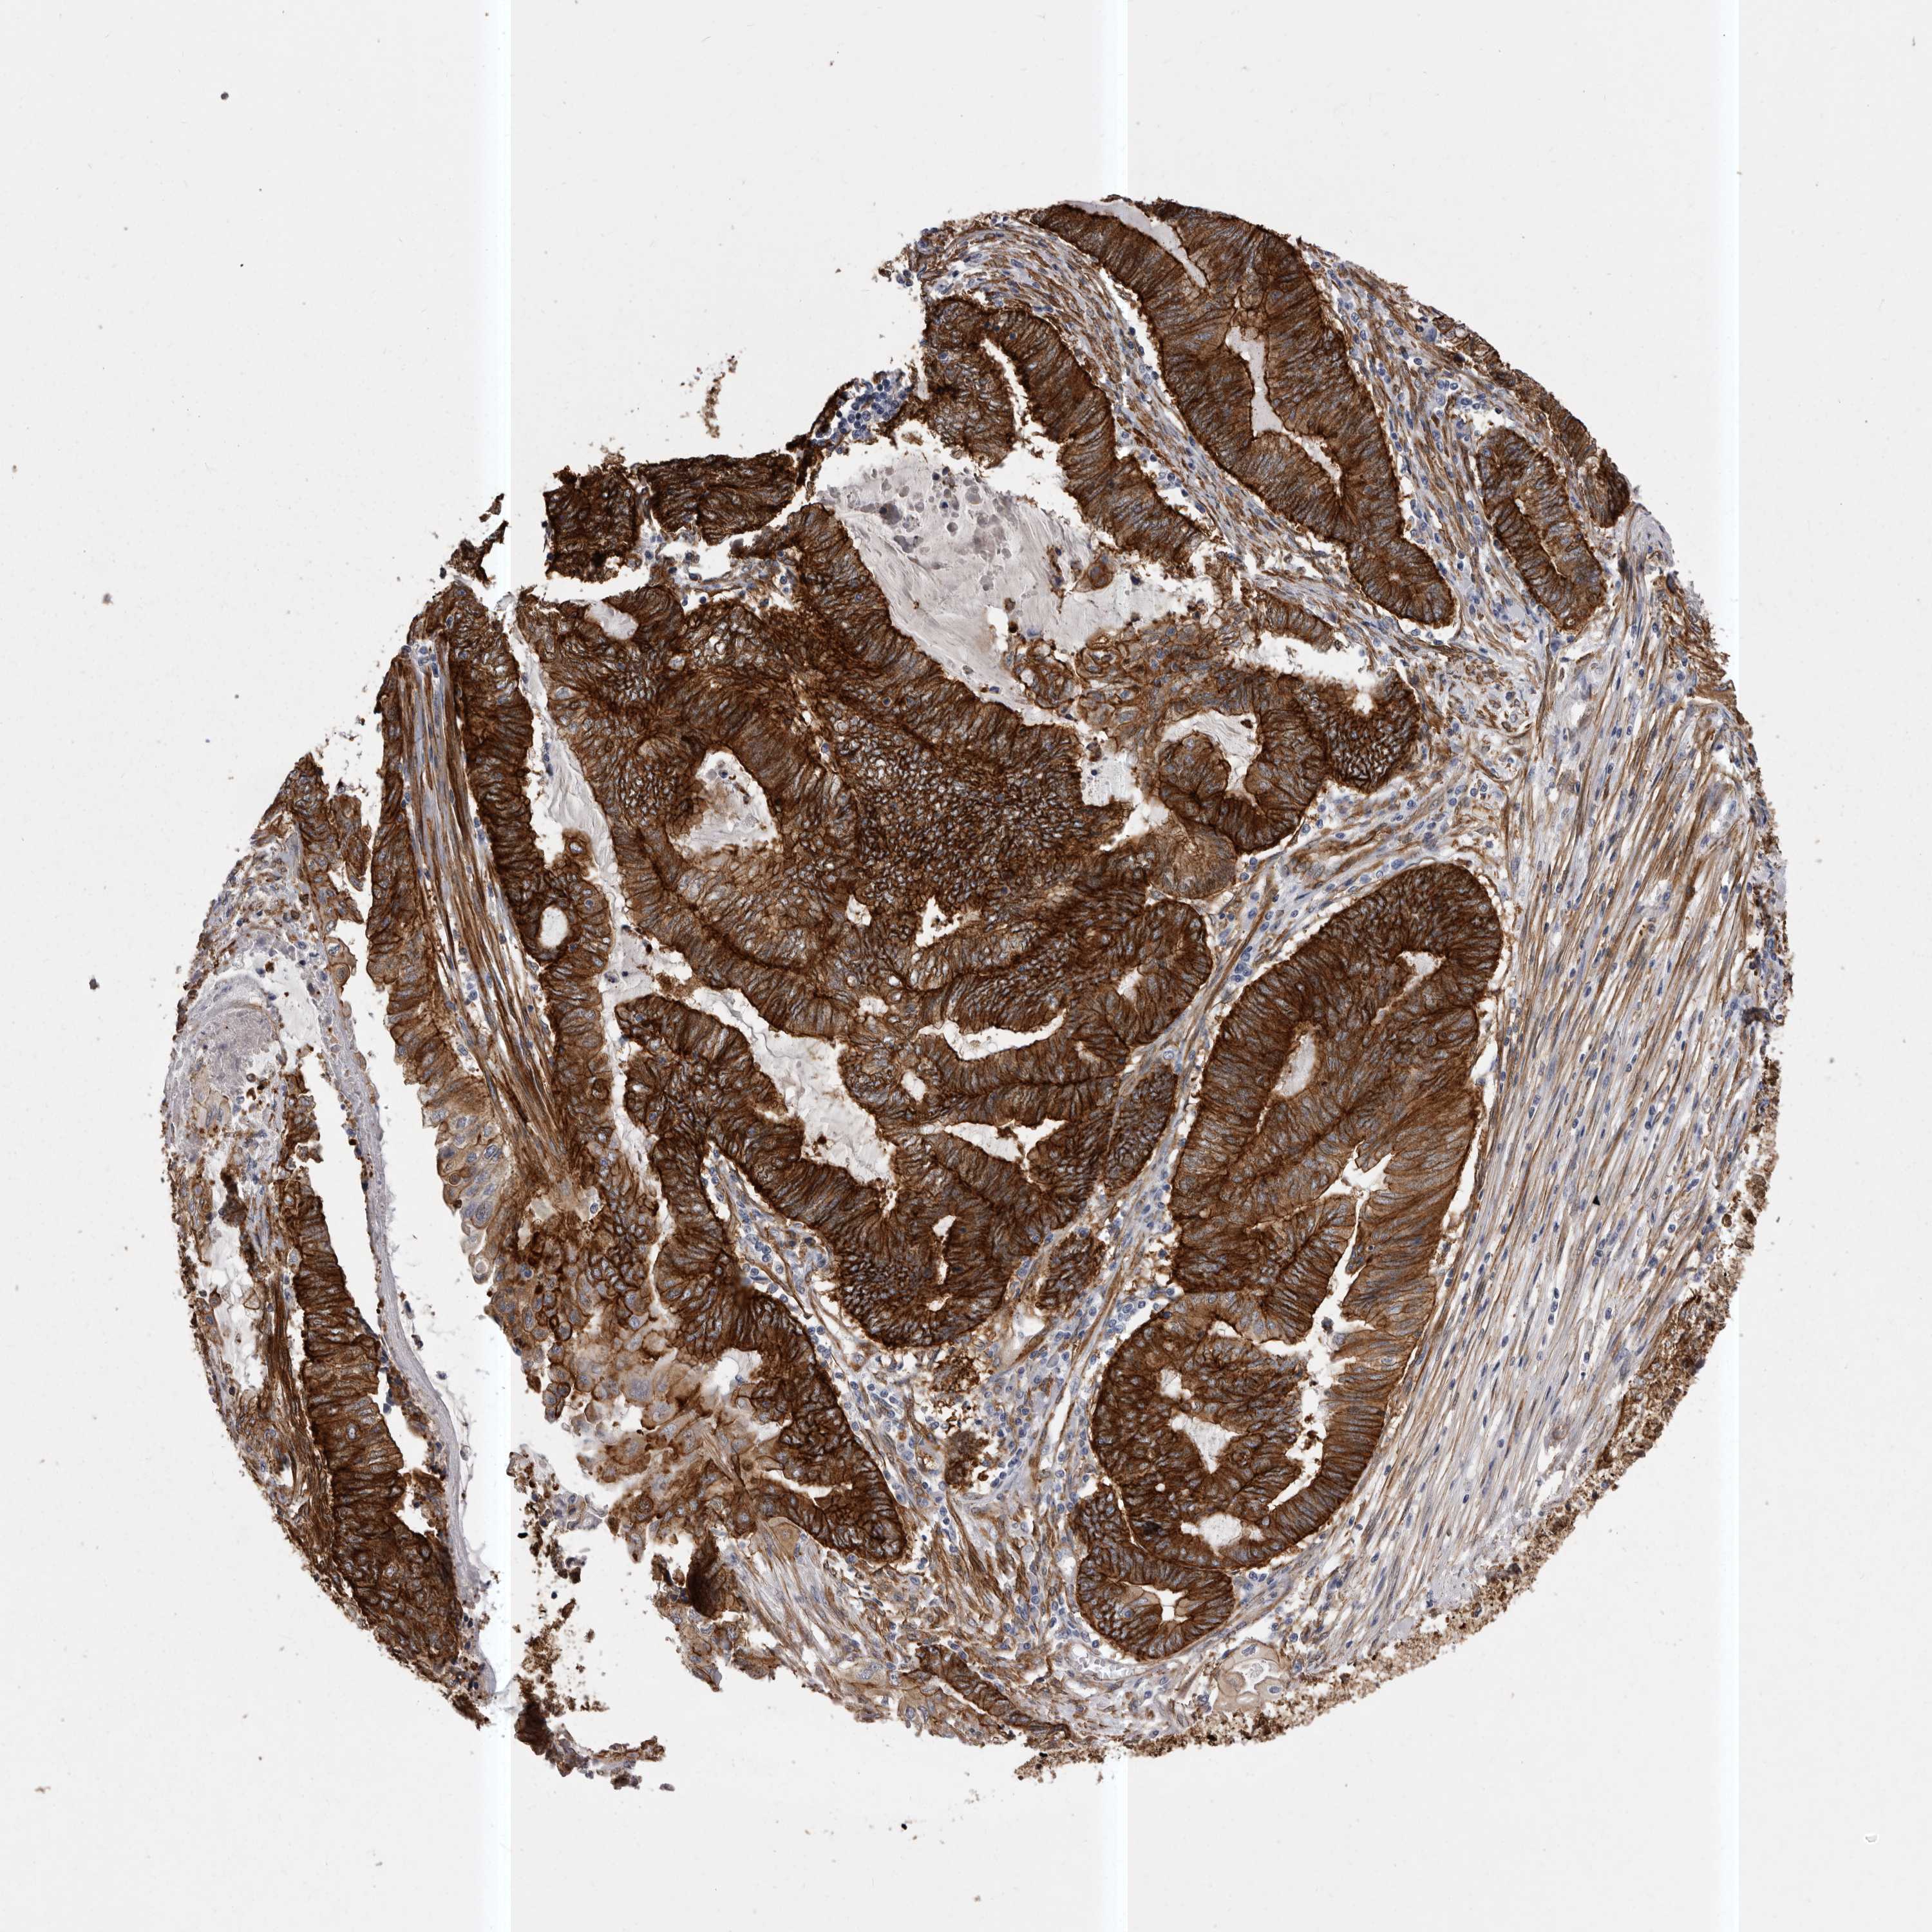

ENDOMETRIAL CANCER - Protein expressioni

A mouse-over function shows sample information and annotation data. Click on an image to view it in a full screen mode. Samples can be filtered based on level of antibody staining by selecting one or several of the following categories: high, medium, low and not detected. The assay and annotation is described here.

Note that samples used for immunohistochemistry by the Human Protein Atlas do not correspond to samples in the TCGA dataset.

Antibody stainingi

Antibody staining in the annotated cell types in the current human tissue is reported as not detected, low, medium, or high, based on conventional immunohistochemistry profiling in selected tissues. This score is based on the combination of the staining intensity and fraction of stained cells.

Each image is clickable and will lead to virtual microscopy that enables deeper exploration of all samples and also displays staining intensity scores, fraction scores and subcellular localization as well as patient and tissue information for each sample.

Antibody HPA028448

Antibody HPA028696

Staining

High

Medium

Low

Not detected

Intensity

Strong

Moderate

Weak

Negative

Quantity

>75%

75%-25%

<25%

None

Location

Nuclear

Cytoplasmic/membranous

Cytoplasmic/membranous,nuclear

Adenocarcinoma, NOS

Adenocarcinoma, metastatic, NOS